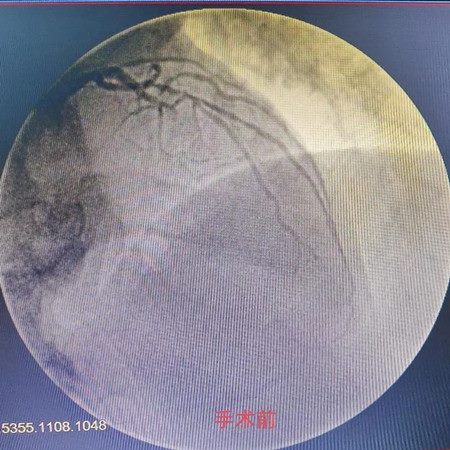

心肌梗死是致命的心血管急症,救治的核心环节是开通闭塞的血管。病人情况危急,时间就是生命,梁海军主任及黄斌副主任立即决定行急诊冠脉造影检查及冠脉内介入治疗,在迅速和患者家属沟通,征得家属同意后患者很快被推入导管室,急诊行冠脉造影结果示左前降支近中段闭塞,前向血流TIMI0级,急性心肌梗死诊断明确。

经与家属协商并签字后决定对左前降支中段闭塞处行急诊PCI术植入支架2枚,前降支远段血流恢复TIMI3级。